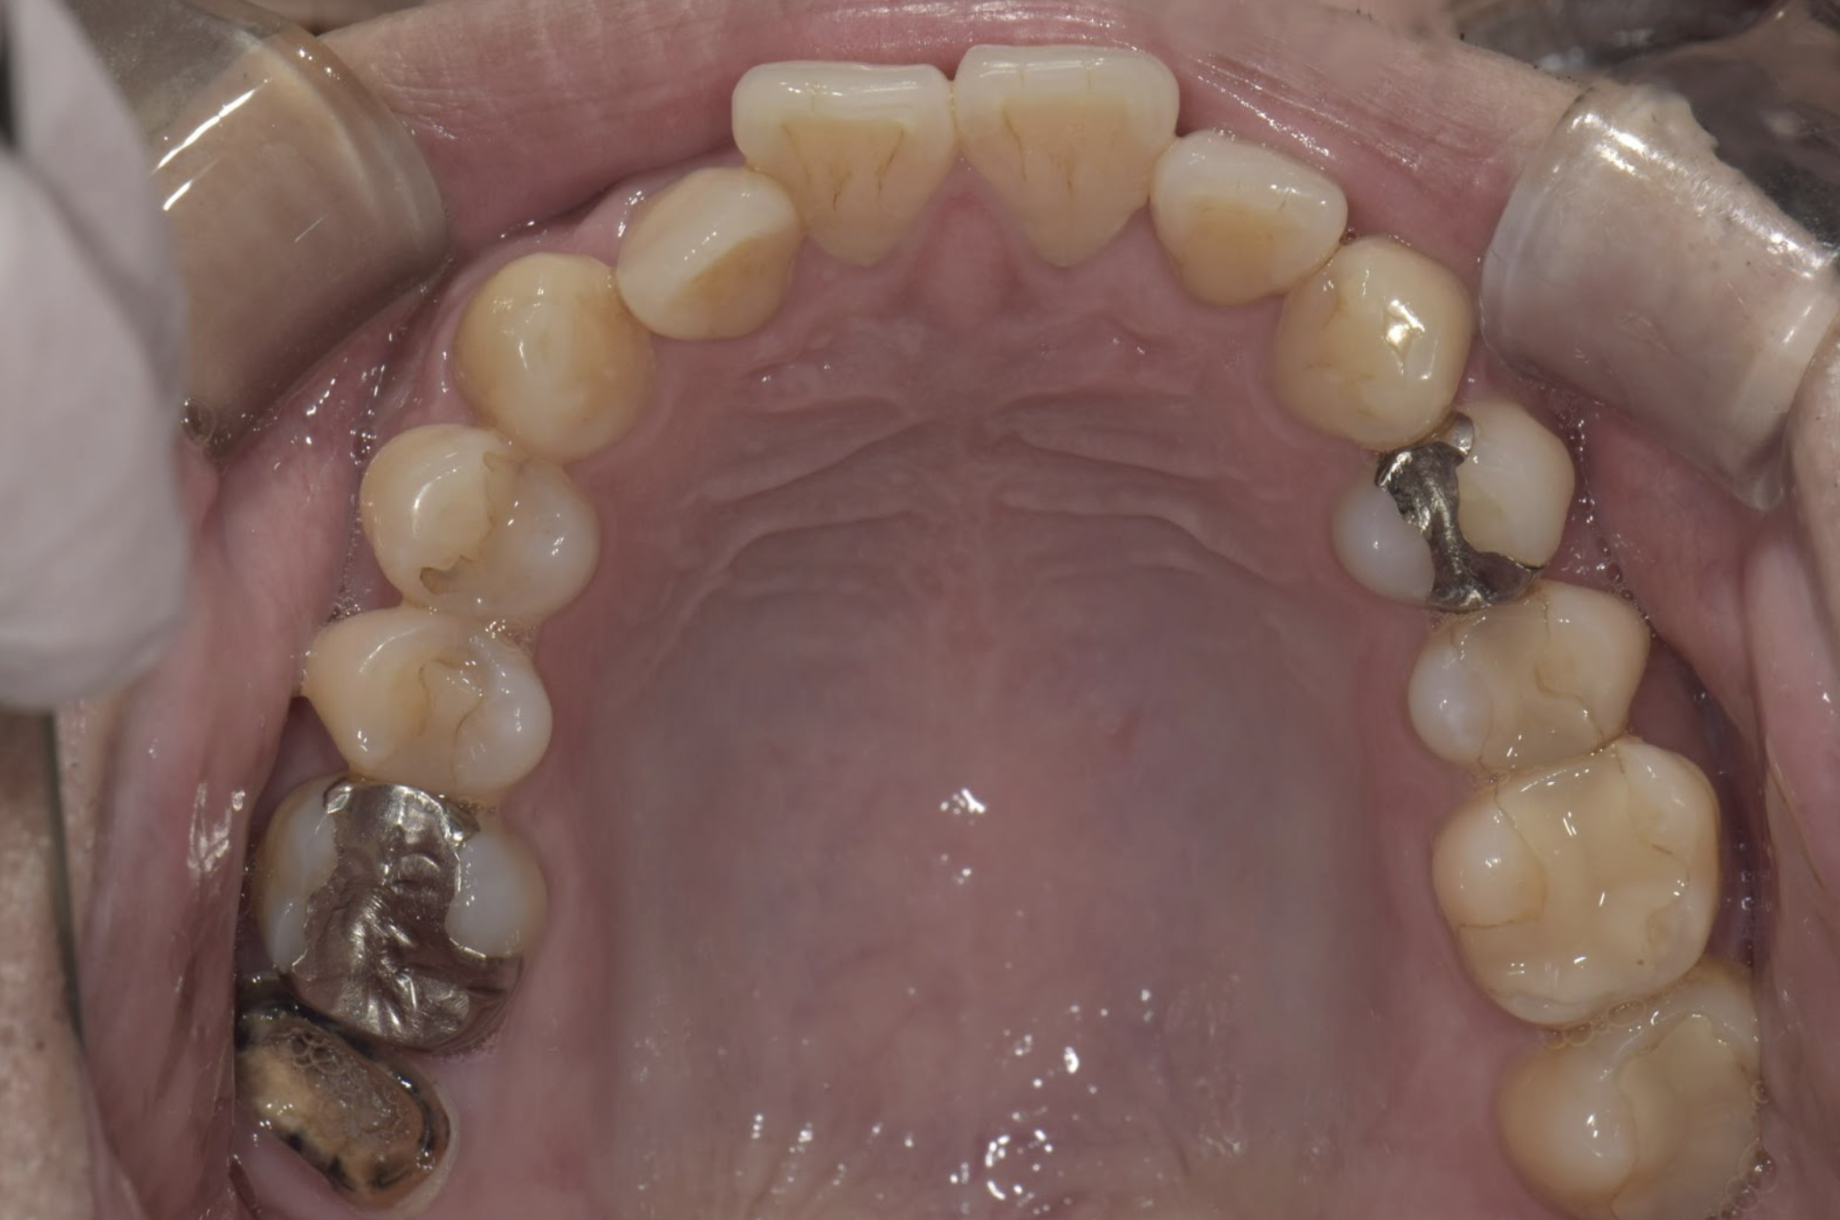

セレックの症例 2019.07.17セレックの症例 セレックとは欠損した歯に対して、セラミック素材による歯の修復を指し、CAD/CAMを用いて設計され、より歯に馴染むように作製されます。初診時…4本セレックセレックスキャン前…(1時間の形作り)セレックセット…... 続きを読む